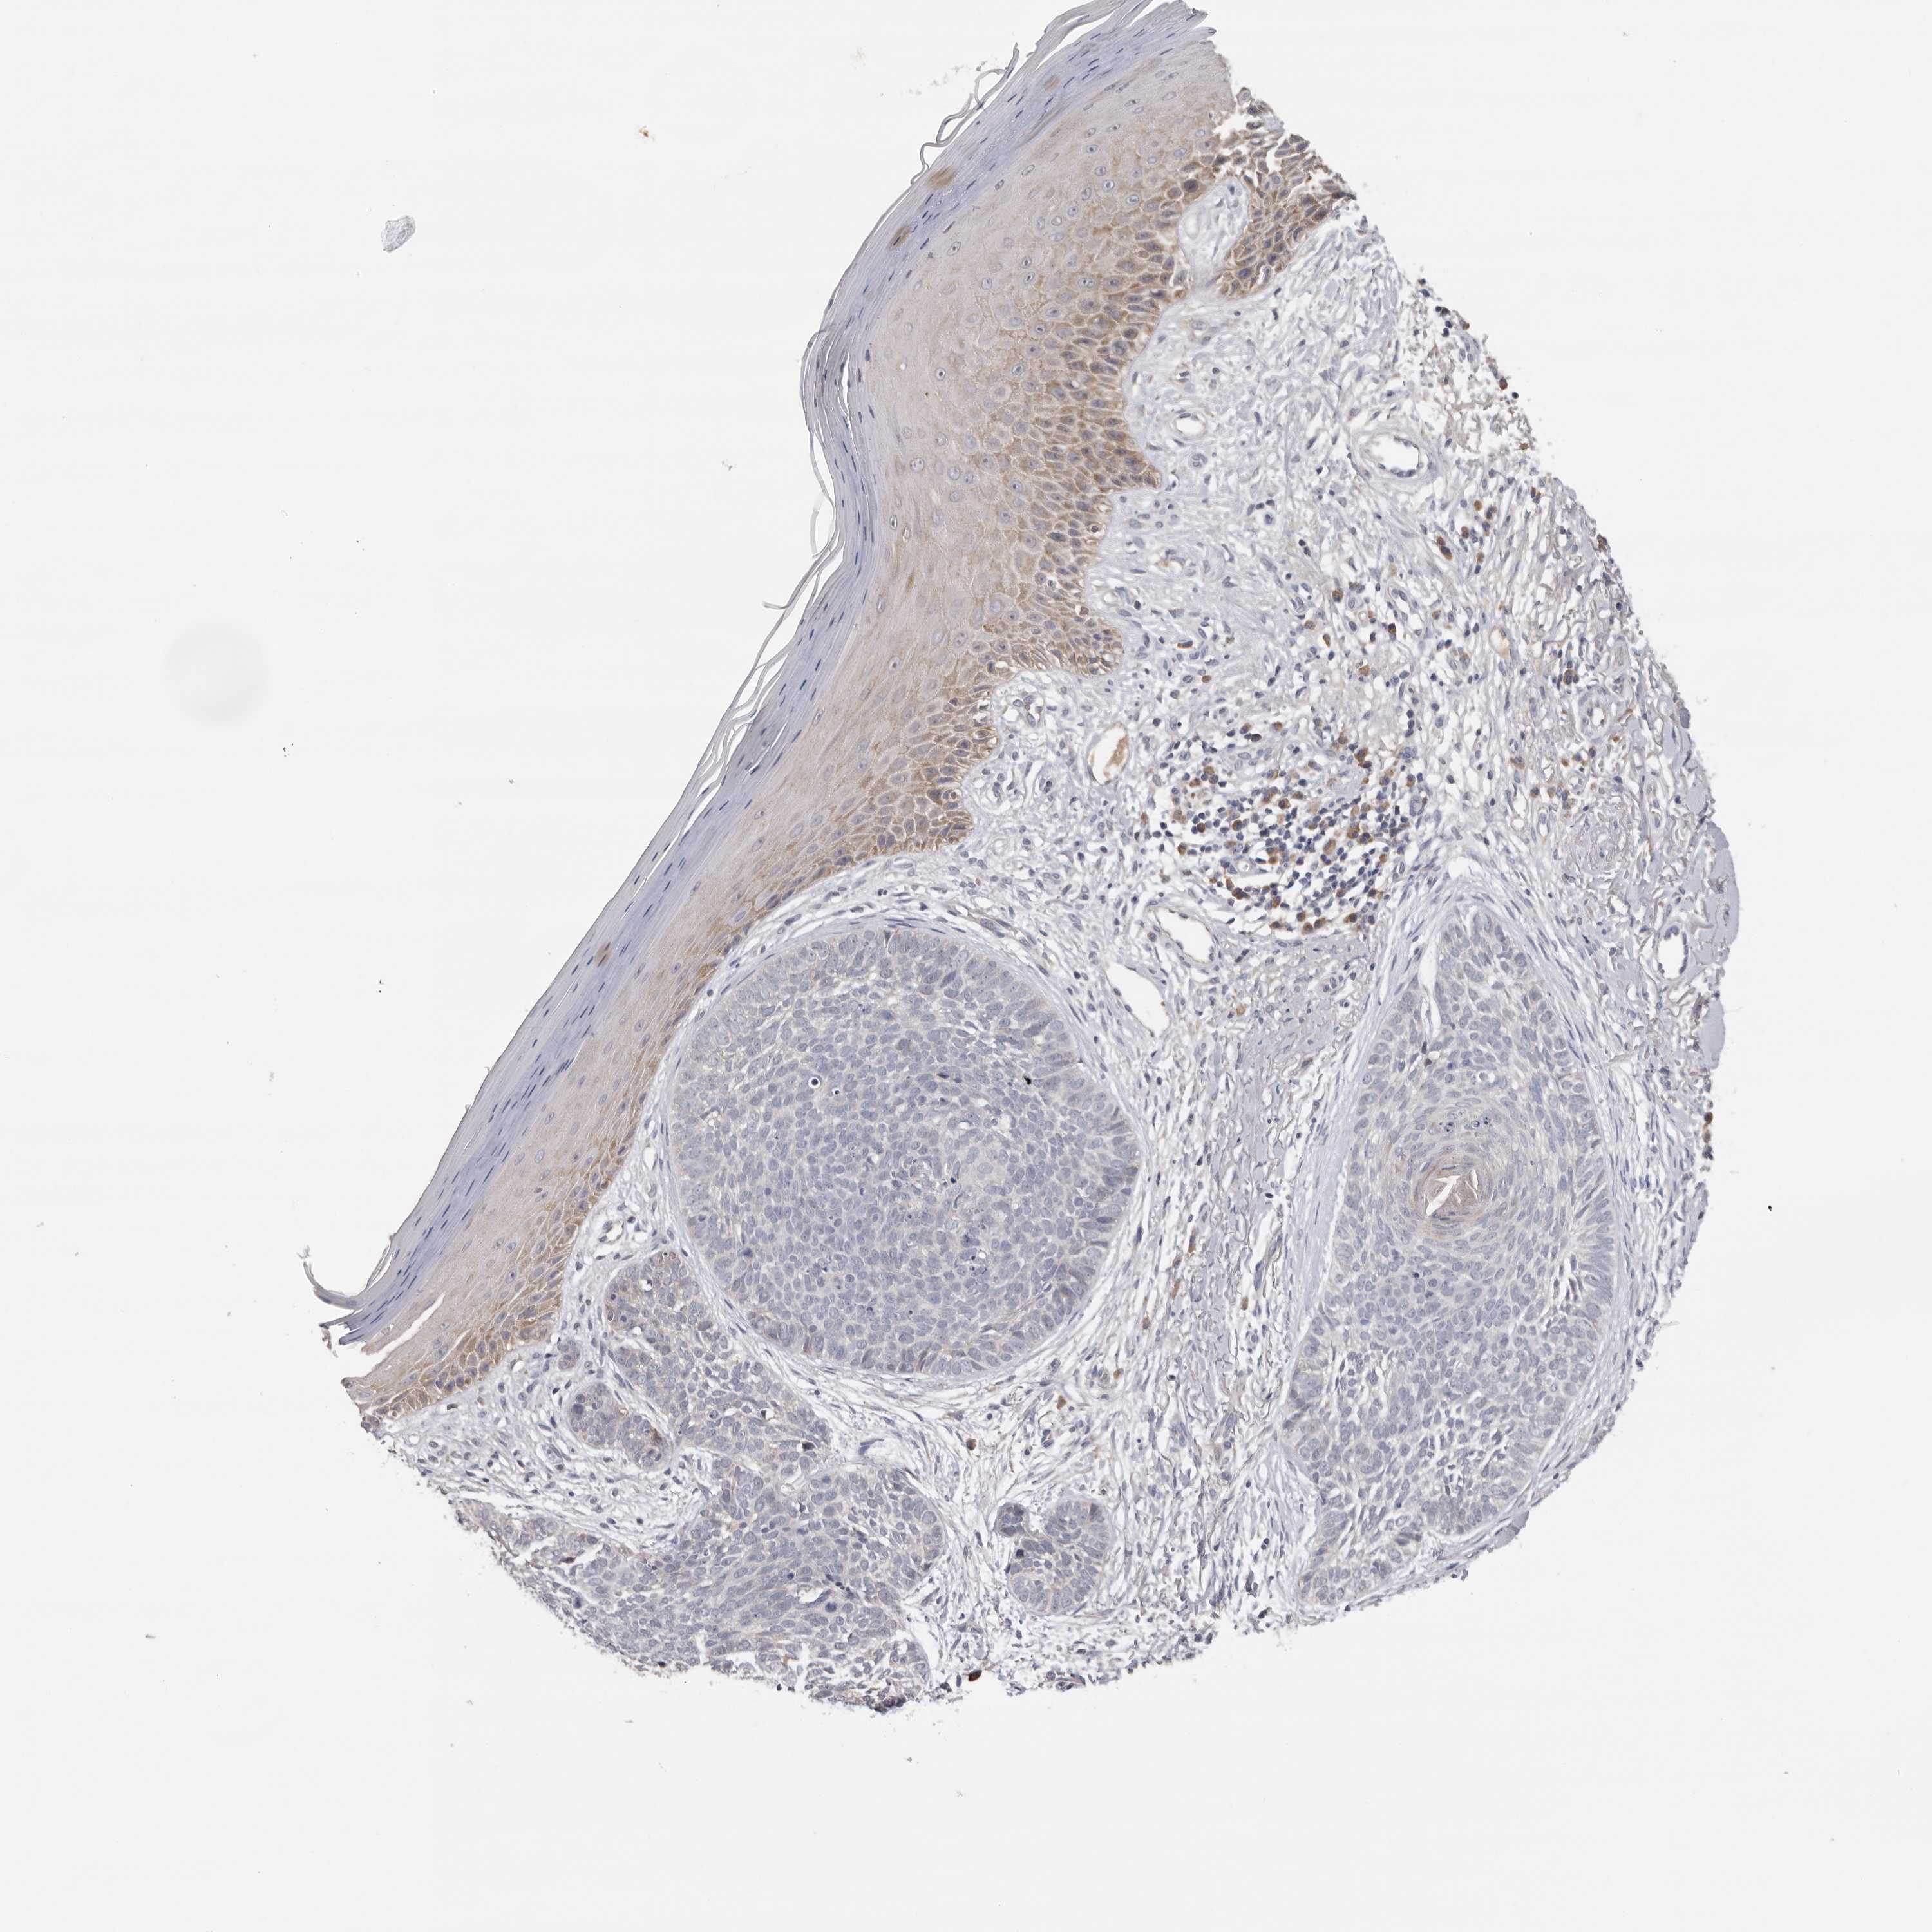

Basal cell and squamous cell cancer

SKIN CANCER - Protein expressioni

A mouse-over function shows sample information and annotation data. Click on an image to view it in a full screen mode. Samples can be filtered based on level of antibody staining by selecting one or several of the following categories: high, medium, low and not detected. The assay and annotation is described here.

Antibody stainingi

Antibody staining in the annotated cell types in the current human tissue is reported as not detected, low, medium, or high, based on conventional immunohistochemistry profiling in selected tissues. This score is based on the combination of the staining intensity and fraction of stained cells.

Each image is clickable and will lead to virtual microscopy that enables deeper exploration of all samples and also displays staining intensity scores, fraction scores and subcellular localization as well as patient and tissue information for each sample.

Antibody HPA023081

Antibody HPA023103

Antibody HPA024795

Staining

High

Medium

Low

Not detected

Intensity

Strong

Moderate

Weak

Negative

Quantity

>75%

75%-25%

<25%

None

Location

Nuclear

Cytoplasmic/membranous

Cytoplasmic/membranous,nuclear

Squamous cell carcinoma, NOS